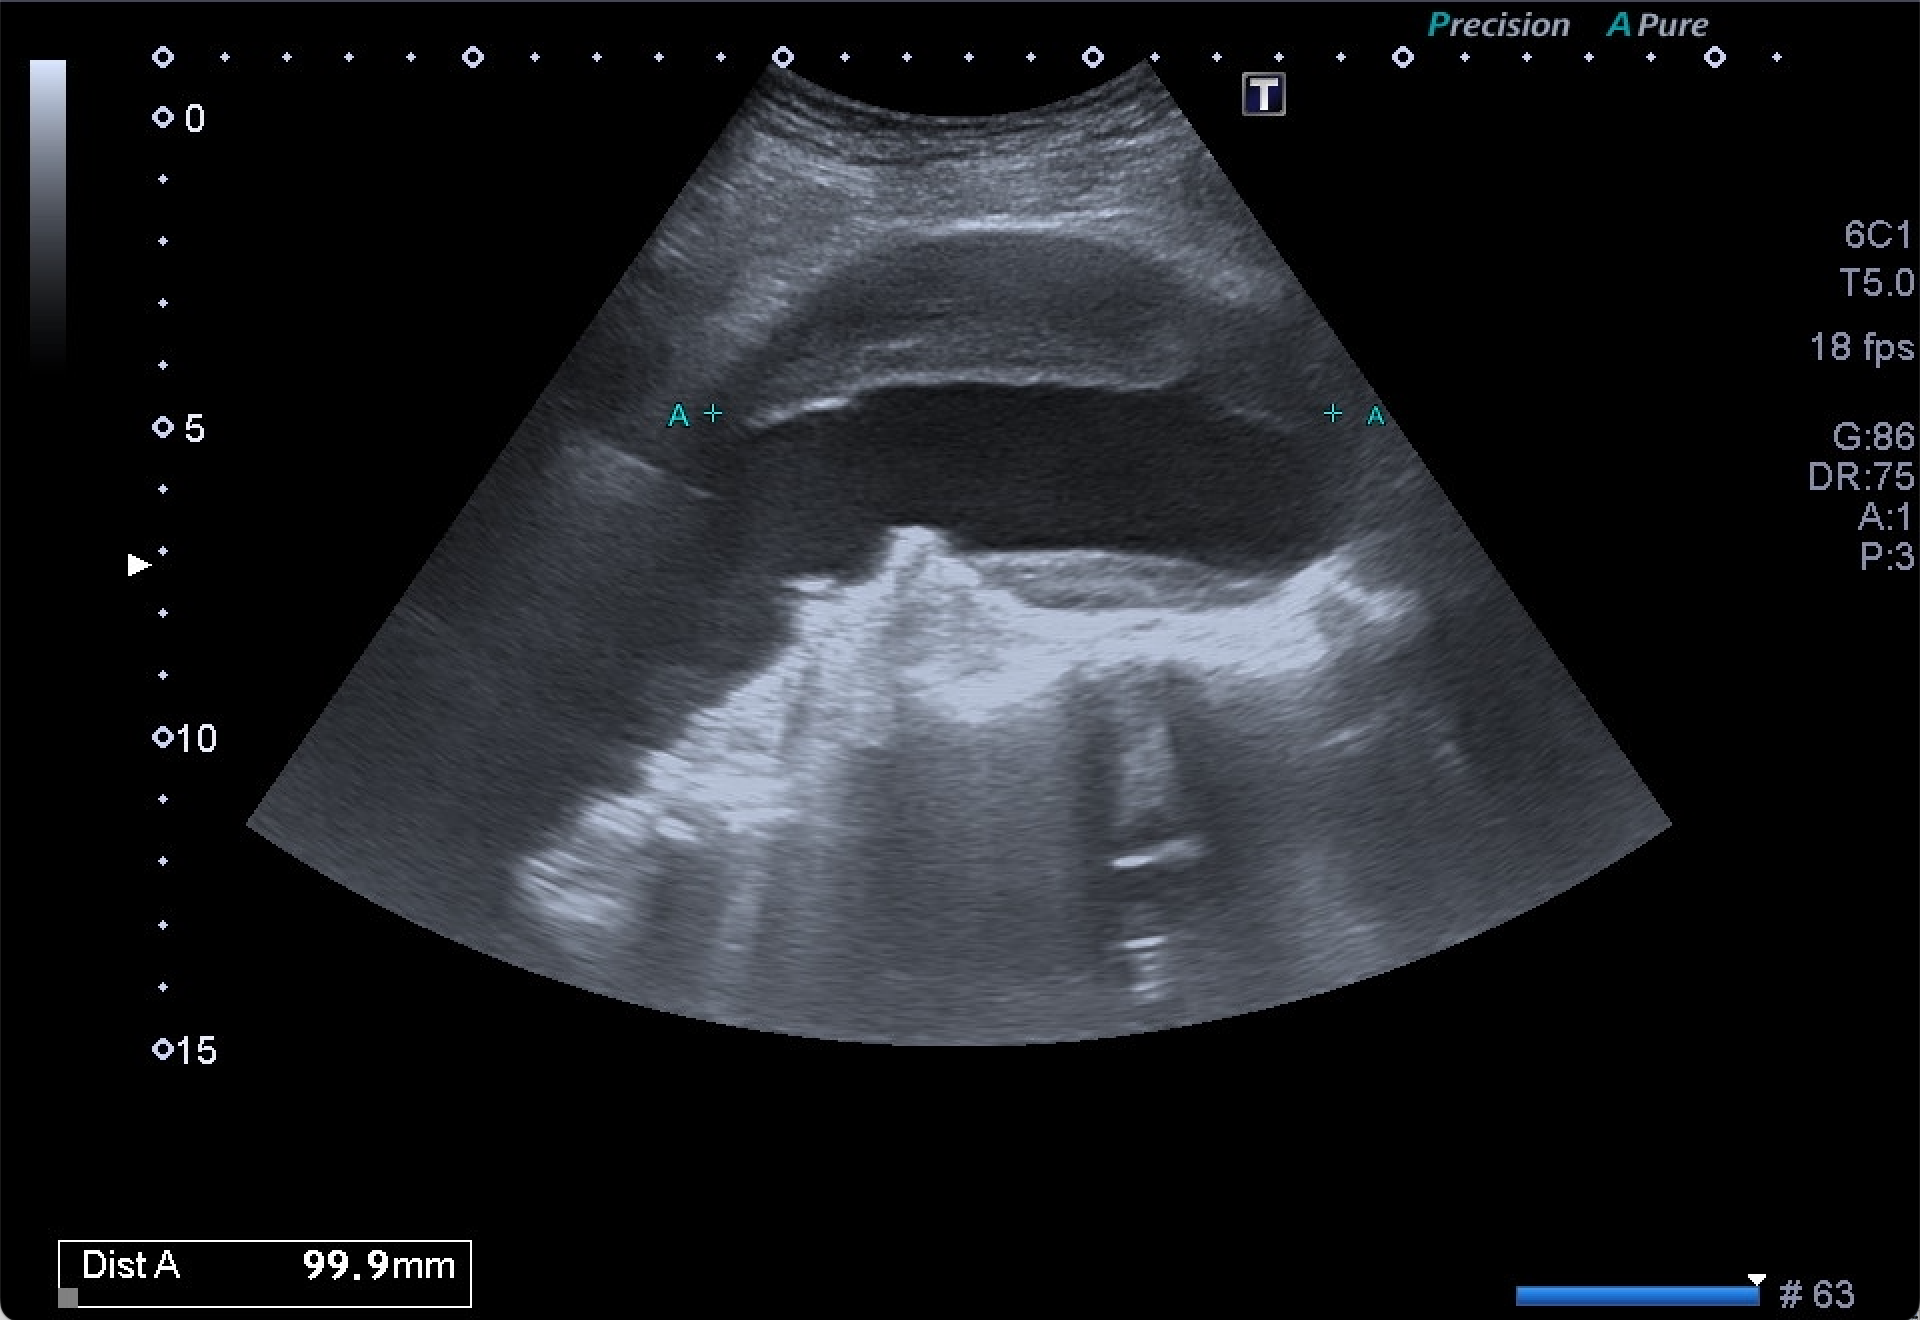

Destaca la visualización de probable litiasis renal derecha, junto con el hallazgo incidental de aneurisma de aorta abdominal, de unos 5,8 cm de diámetro máximo en el plano axial, el cual presenta trombo mural.

Dados los hallazgos, se completa estudio con AngioTC, confirmando la existencia de aneurisma infrarrenal de 6 mm de diámetro mayor, junto con litiasis renal derecha de 5,5 mm y dilatación de la pelvis renal.